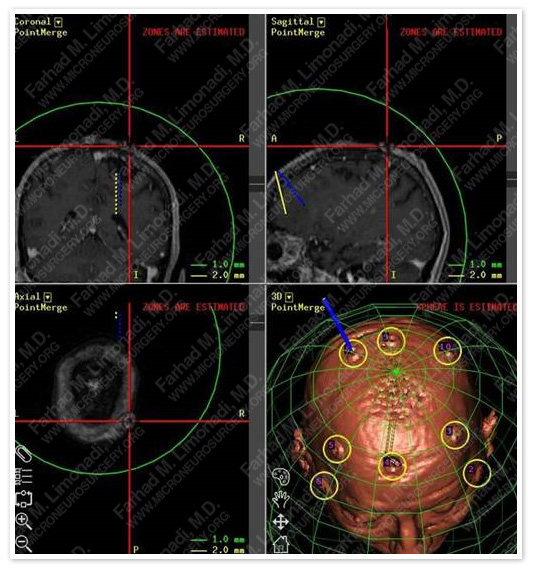

Computer Navigation

Comptuer navigation was used to determine the precise location of the tumor and important adjacent structure.